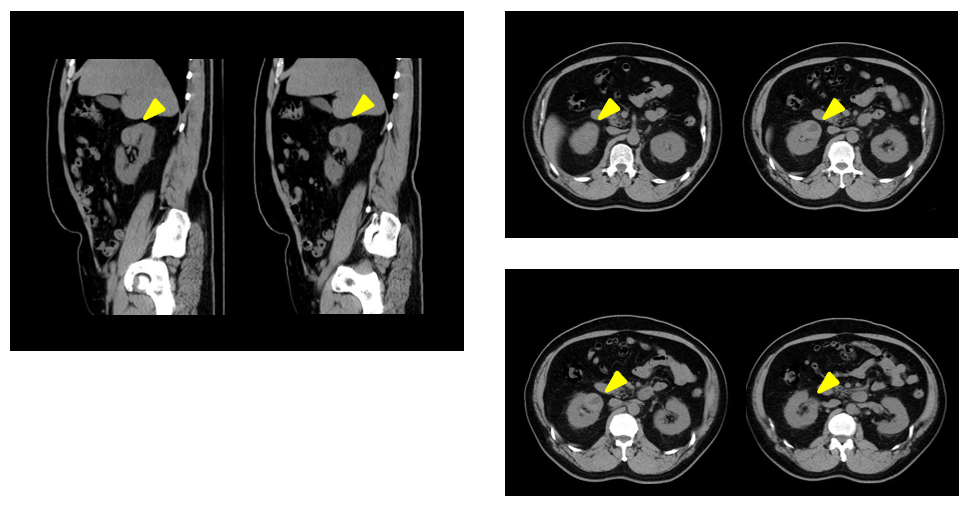

画質に関しても満足しています。1.25㎜断面で撮像されているので、腹部の標準プロトコルには、 アキシャル画像だけでなくサジタル断面も同時に再構成するプロトコルを用いています。これらの画質は ノイズも少なく、とてもシャープです。これにより臓器や病変の連続性がよく描出されており、先日もCT検査で 腎腫瘍疑いの事例があり、病変はクリアに描出されていました。

cv_otaru_hinyouki_02_big.png

CT Revolution ACT 右腎臓癌の臨床画像